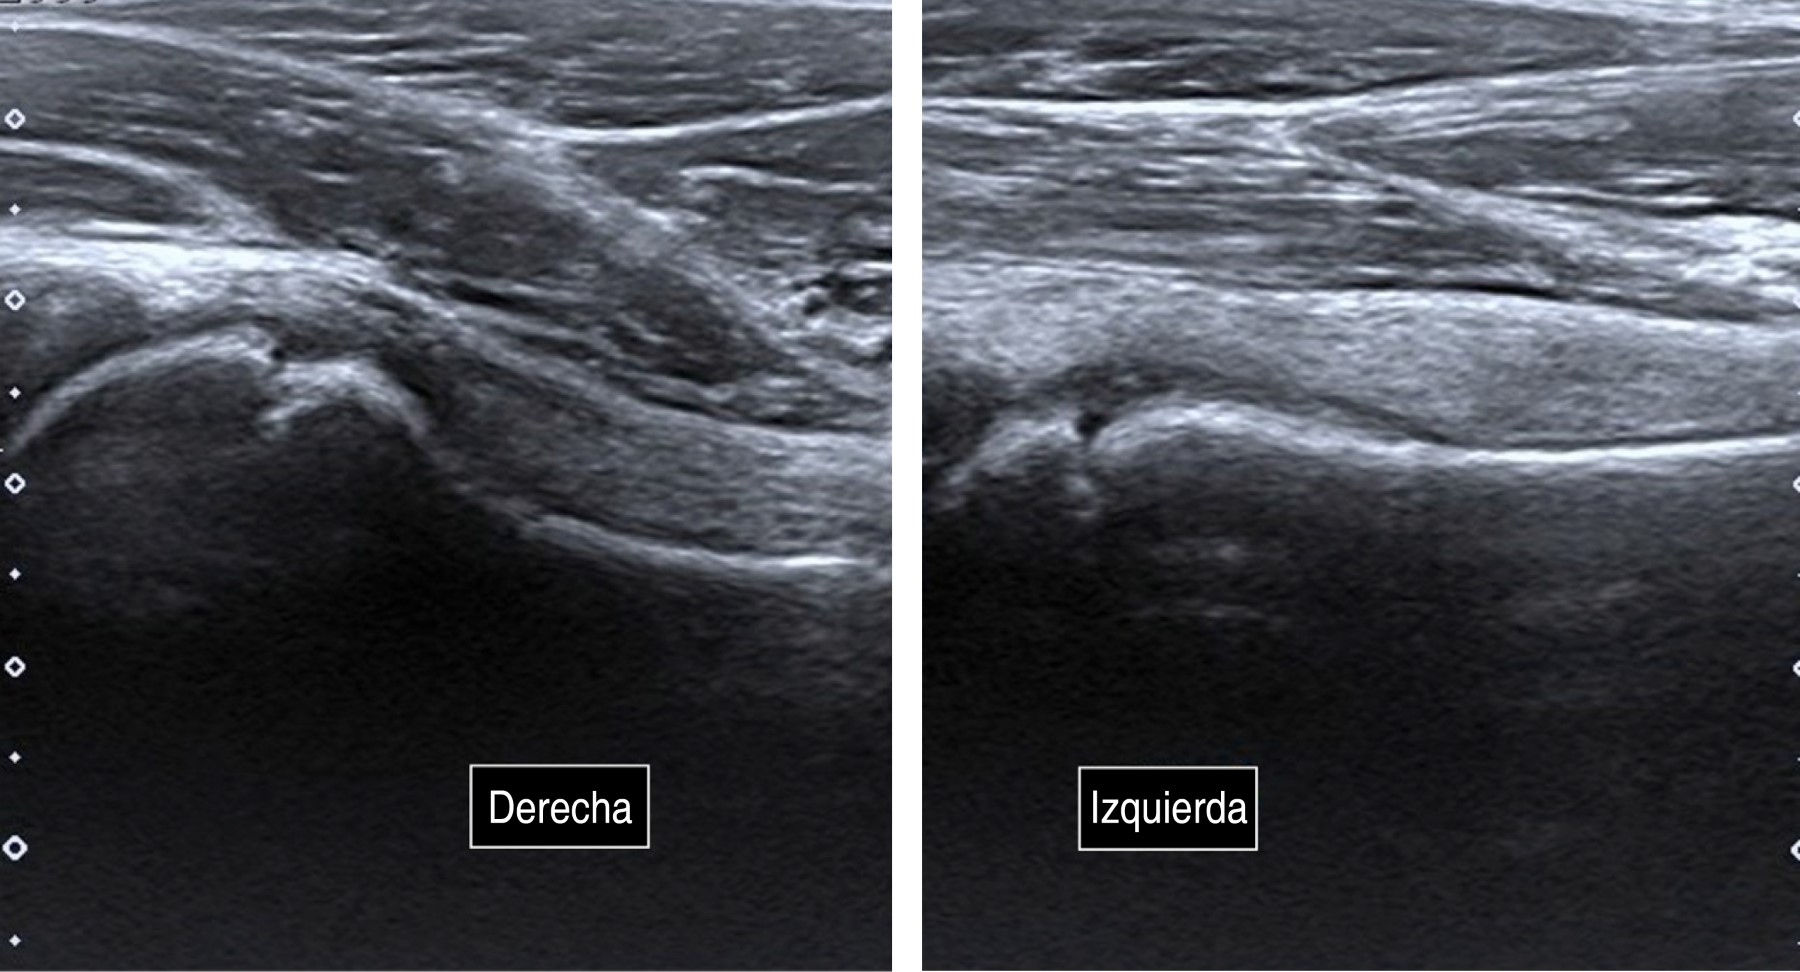

Transient synovitis after COVID-19

During the recent COVID-19 world pandemic, we report the case of a 12-year-old patient referred to our hospital with hip pain and limping who had been diagnosed with COVID-19 two weeks before. Altogether, normal X-ray and laboratory findings, alongside an ultrasound compatible with synovitis let us diagnose transient synovitis. The patient was treated with anti-inflammatory drugs and rest, with satisfactory evolution. Conclusions: Coronavirus led to a proinflammatory situation which might be cause of atypical symptoms. We described one of the first cases of post SARS-CoV-2 transient synovitis. However, more studies are needed to stablish causal relationship.

Figure 2